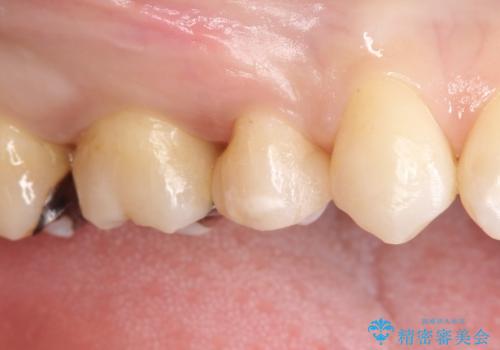

- 定期検診にて虫歯を見つけ、メタルボンドクラウンにて修復補綴治療を行なっております。

歯肉縁下まで虫歯が進行していたため歯周外科を併用して治療を行なっております。

メタルボンドクラウンは内側に金属のフレーム、外側にセラミックを使用した被せ物です。